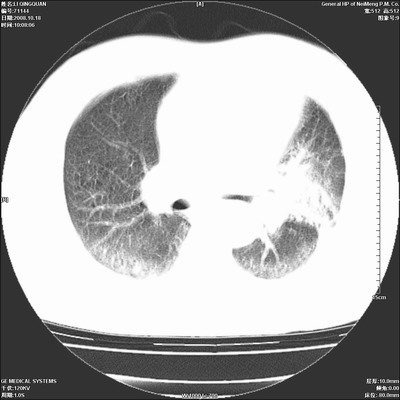

以下是引用duguo在2008-10-19 13:59:00的发言:[br]左肺上叶支气管狭窄,首先考虑中心型肺癌伴阻塞性肺炎\\肺不张.

以下是引用ybing在2008-10-19 12:58:00的发言:[br]左肺上叶阻塞性炎症-建议支气管镜进一步检查除外中央型肺癌

以下是引用随光逐影在2008-10-19 14:31:00的发言:[br]考虑左肺中央型肺癌并左肺上叶阻塞性肺炎,肺不张。